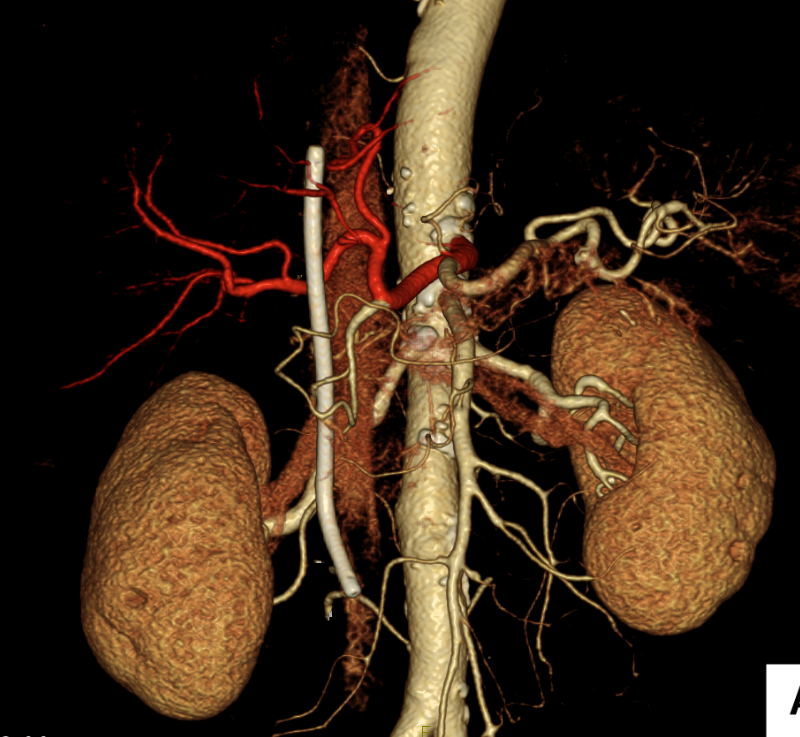

CT画像(肝門部領域胆管がん)